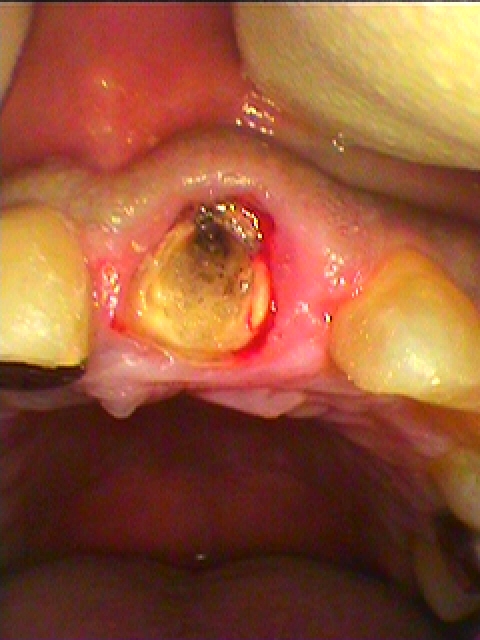

お知らせ|広島市安佐南区の歯科医院 > お知らせ トップ お知らせ・ブログ お知らせ スタッフブログ お知らせ お知らせ 2021/09/18 左下の2本 インプラント埋入の埋入位置、角度、深度すべてはCTにて行っています 50代女性 お知らせ 2021/09/17 左下の大臼歯部のインプラント埋入 50代後半女性 お知らせ 2021/09/17 2か月たってプロビジョナルを入れて歯肉形態を付与していきます 40代男性 お知らせ 2021/09/16 左上前歯部の歯牙破折により抜歯即時インプラント埋入へ 40代男性 お知らせ 2021/09/16 左上の1番 歯が動くとのこと 40代男性 保険の前歯が入っていました お知らせ 2021/09/16 右上の3番が先天性欠損で萌出してきませんでした 乳歯を持たせていたのですが抜歯となりました 40代女性 お知らせ 2021/09/15 3ヶ月後、上部構造を建てていきます インプラントでも審美的に仕上がるかが問題です お知らせ 2021/09/15 右上1番が土台ごと脱離 診てほしい 40代女性 ずっと違和感はあった歯になるそうです お知らせ 2021/09/14 左上の上のインプラント埋入は難関とも言えますが、、、 将来入れ歯で過ごすこともいかずインプラントを埋入していきます お知らせ 2021/09/14 左上のインプラント埋入 35歳女性 昔、ブリッジが入っていたが割れてダメになったとのこと << 1 2 3 4 5 … 191 192 193 194 195 … 485 486 487 488 489 >> Web診療予約 初めての方へ 選ばれ続ける理由 院内設備について 歯が痛いしみる一般歯科 歯がぐらぐらする歯周病 健康な歯を保ちたい予防歯科 子供の虫歯予防をしたい小児歯科 銀歯をセラミックに審美歯科 白い歯を目指しませんか?ホワイトニング 矯正専門医がいるので安心矯正歯科 抜けた歯を補いたいインプラント・入れ歯 医院案内 スタッフ紹介 メリィハウス歯科クリニックオフィシャルホームページ ラベンダー歯科クリニックオフィシャルホームページ お知らせ・ブログ ホーム 診療科目 一般歯科 歯周病治療 予防治療 小児歯科 審美治療 ホワイトニング 矯正歯科 入れ歯・インプラント マウスピース矯正 初めての方へ 院長・スタッフ 設備紹介 医院案内・アクセス メニューを閉じる